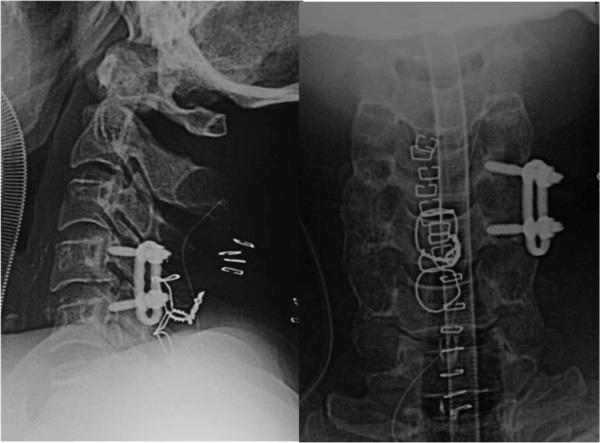

A 41-year-old Asian man presented with C4 to C5 distractive flexion injury manifesting with quadriplegia and anesthesia below his C3 cord level (including phrenic nerve paralysis), and bowel and bladder dysfunction. Magnetic resonance angiography and computed tomography angiography showed left extracranial vertebral artery occlusion and patent contralateral vertebral artery. He was observed without antiplatelet and/or anticoagulation therapy, and underwent surgery (open reduction and internal fusion of C4 to C5, and tracheostomy) 8 hours after the injury. After surgery, supraspinal symptoms such as left horizontal nystagmus and left homonymous hemianopsia led to cranial computed tomography and magnetic resonance imaging, which showed left-side cerebellar infarction in his posterior inferior cerebellar artery territory and right-side posterior cerebral artery infarction. Magnetic resonance angiography and computed tomography angiography demonstrated patent bilateral vertebral artery (but hypoplastic right vertebral artery) and occluded right posterior cerebral artery. His injured vertebral artery was treated conservatively, which did not cause any other ischemic complications.

一名41岁的亚洲男性,因C4至C5椎体牵张屈曲损伤就诊,表现为四肢瘫痪、C3脊髓水平以下感觉缺失(包括膈神经麻痹)以及肠道和膀胱功能障碍。磁共振血管造影和计算机断层血管造影显示左侧颅外椎动脉闭塞,对侧椎动脉通畅。在未进行抗血小板和/或抗凝治疗的情况下对其进行观察,并在受伤8小时后进行了手术(C4至C5椎体切开复位内固定术和气管切开术)。术后,出现了诸如左侧水平眼震和左侧同向性偏盲等脊髓以上症状,遂进行头颅计算机断层扫描和磁共振成像检查,结果显示左侧小脑后下动脉供血区小脑梗死以及右侧大脑后动脉梗死。磁共振血管造影和计算机断层血管造影显示双侧椎动脉通畅(但右侧椎动脉发育不良)以及右侧大脑后动脉闭塞。对其受伤的椎动脉采取了保守治疗,未引发任何其他缺血性并发症。